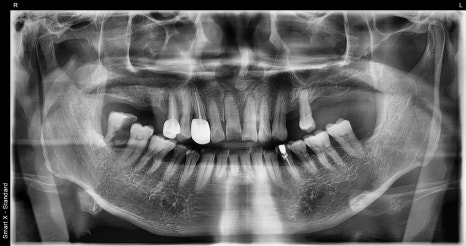

🖼️ Lip trauma photo / Front tooth fracture and fixation photo / X-ray photo

Lip laceration immediately after the trauma / Initial emergency treatment photo showing fixation of the dislocated front tooth

Full panoramic X-ray taken at the first visit